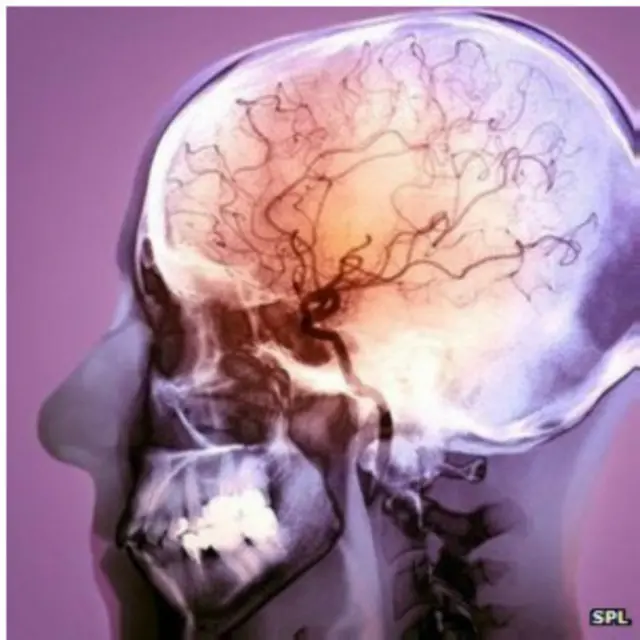

Инсульт происходит в мозге в результате кислородной недостаточности, вызванной прекращением кровоснабжения либо недостаточным кровообращением.

При ишемическом инсульте, который диагностируется в 80% случаев, кровоснабжение мозга нарушается из-за закупорки сосуда сгустком крови. При геморрагическом инсульте из-за разрыва сосуда происходит кровоизлияние в мозг.

К геморрагическому инсульту нередко приводят врожденные дефекты системы кровообращения. В этом случае "заложенная в мозг" бомба с часовым механизмом может взорваться в любой момент.

Один из примеров таких "бомб" - артериовенозная мальформация, когда артерии напрямую связаны с венами из-за отсутствия капиллярной сети, а значит давление внутри них слишком велико для кровеносных сосудов. Когда не выдержав его, сосуды лопаются, происходит кровоизлияние в мозг.